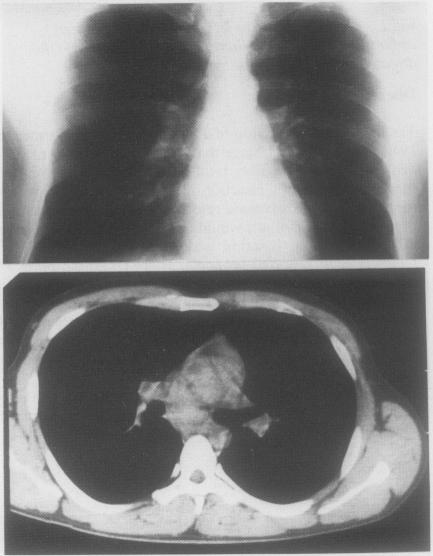

Diagnosis and treatment of a bronchogenic cyst using transbronchial needle aspiration.

Thorax. 1986 Apr;41(4):326-7. doi: 10.1136/thx.41.4.326.

Diagnosis and treatment of a bronchogenic cyst using transbronchial needle aspiration.经支气管针吸活检术诊断和治疗支气管源性囊肿